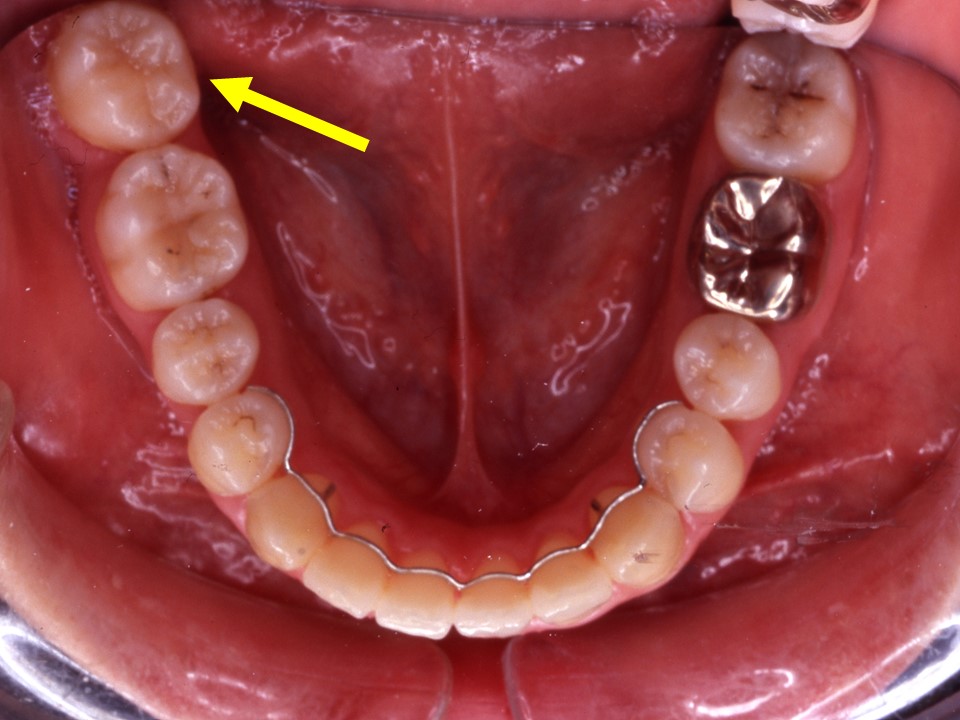

下顎咬合面。下顎第二大臼歯は、深い虫歯で保存不可能のため、抜歯となった(矢印)。